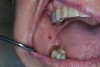

With reduced salivary flow, the mucosa can appear dry and even adhere to examination gloves, gauze, or mouth mirror. The lingual dorsum may exhibit fissures and elongation of the filiform papillae, often described as a coated or hairy tongue (Figure 1). Dental caries may be present, especially in the cervical areas or root caries (Figure 2). Small erythematous macules on the buccal mucosa represent bite marks, which are common with inadequate saliva (Figure 3). Gingivitis (Figure 4), gingival recession, and periodontal disease may be present.14,15

Fig 1. White-tan elongated filiform papillae present in a patient with no saliva collected in 5 minutes. Mouth malodor also present.

Figure 1